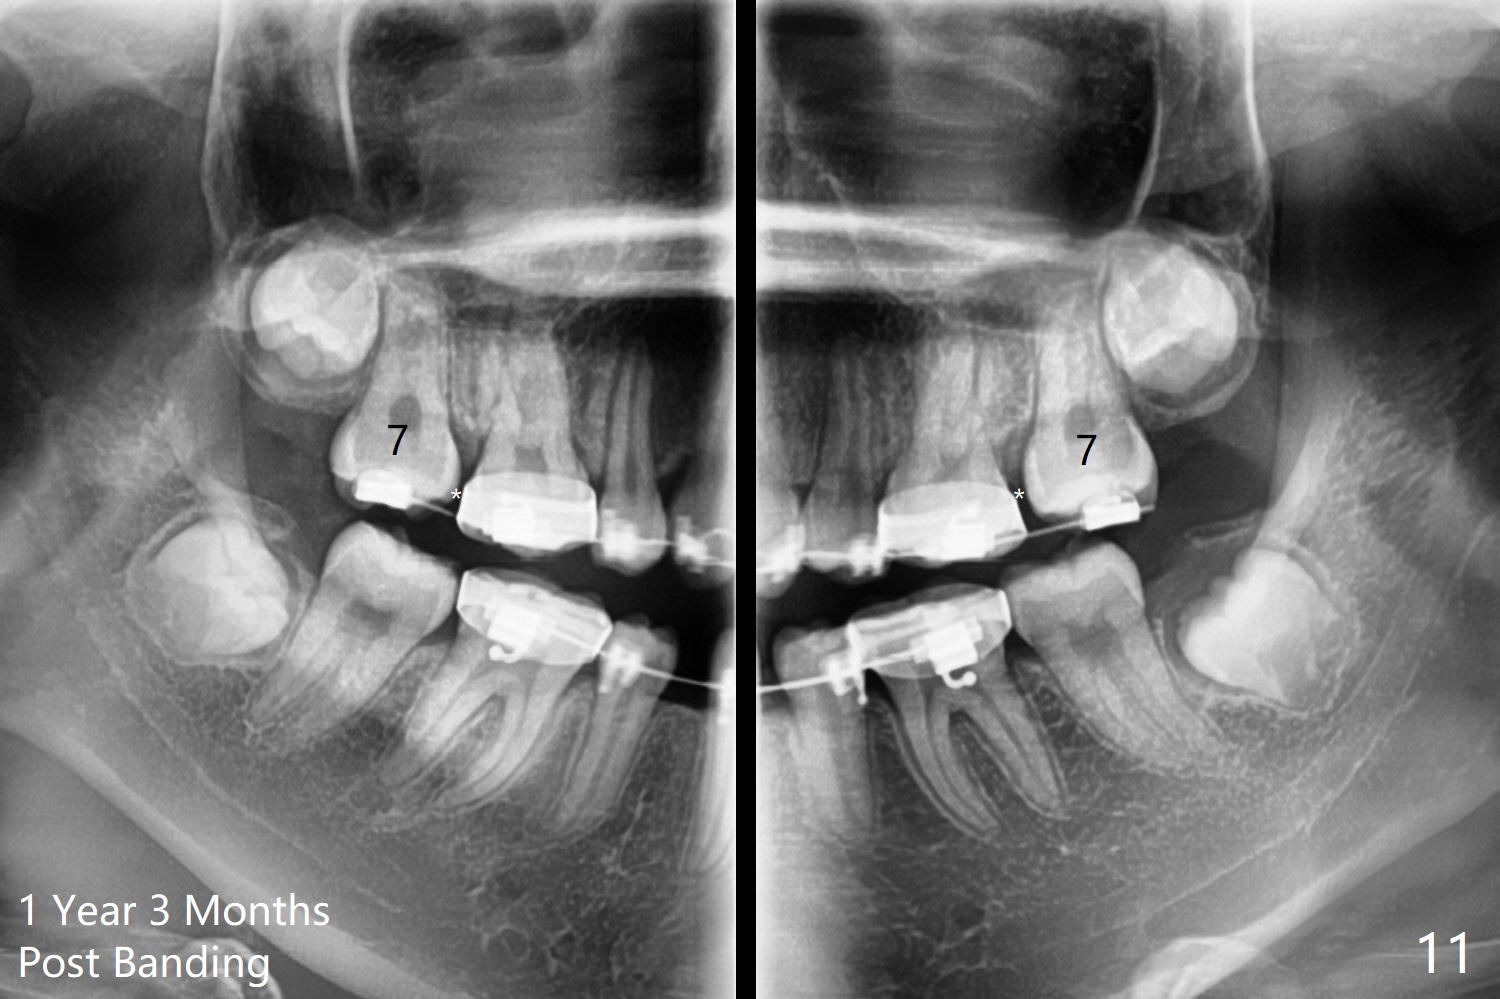

Two weeks post extraction of 4 bicuspids, brackets and bands are placed in 20 teeth (Fig.1-3, 14 niti). No bands are placed at 7s because of short crowns and tight contacts. When 16x16 wires are used, start Class II retraction. The latter is initiated with elastics when 18 ss wires are placed (Fig.4,5). U3s have been distalized with closed springs for 3 months (Fig.6,7). U2s are close to distalization 13 months post banding, 3.5 months post posted wire (Fig,8,9) with overjet (Fig.10). Class II retraction is re-initiated. When the upper incisors are retracted, the anterior overjet remains large. It appears that U6s have been retracted anterior, as indicated by the space between U6/7 (Fig.11), because of no use of U7s as anchors. Brackets are just placed with 18 niti arch wire. They will be retracted distal using the rest of the upper teeth and lower teeth (using Class II retraction) as anchor. There is root resorption of the upper anteriors 2 years 1 month post banding (Fig.12,13).